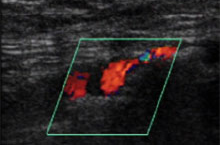

Farbdopplersonographie

Bei der farkodierten Dopplersonographie werden drei Untersuchungsmodi kombiniert. Das Schnittbild erlaubt die morphologische Beurteilung des Gefäßlumens und der Gefäßwand, die Farbkodierung des Blutflusses zeigt Flussrichtung und eventuelle Tubulenzen. Die gleichzeitig registrierte Dopplerkurve zeigt die Flussgeschwindigkeit und eventuelle vorgeschaltete Obstruktionen. Wird direkt in einer Stenose gemessen, ist die Flußgeschwindigkeit erhöht, nach einer Stenose erniedrigt.

Die nichtinvasive Farbdopplersonographie kann bei peripheren Gefäßerkrankungen die Angiographie vor einer Operation oder endovaskulären Intervention in den meisten Fällen ersetzen.